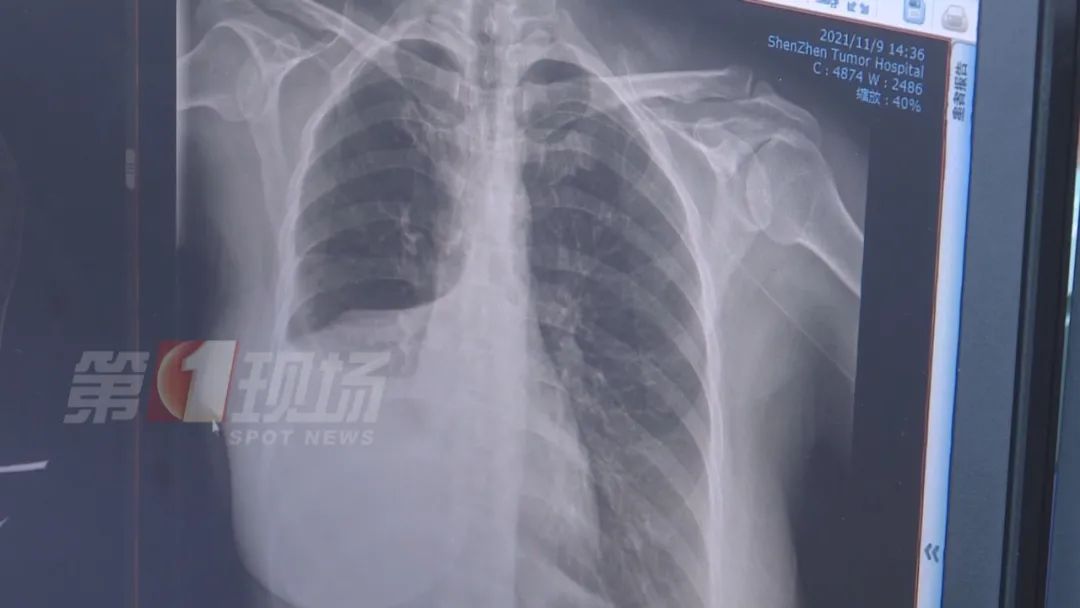

江女士做了增強(qiáng)CT后,確實(shí)發(fā)現(xiàn)肺部有一個(gè)五公分左右的腫瘤,醫(yī)生診斷為肺癌,目前為中期偏早,建議她進(jìn)行切除手術(shù)。